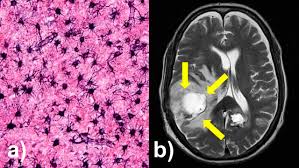

El glioblastoma multiforme (GBM) es el tumor cerebral primario más común en adultos. Su comportamiento invasivo y su resistencia a la radioterapia y quimioterapia lo convierten en un gran desafío clínico.

El cáncer cerebral llamado glioblastoma se caracteriza por su alta heterogeneidad genética, lo que le permite adaptarse rápidamente a los tratamientos. Además, cambia su metabolismo con el tiempo —un fenómeno conocido como “camuflaje metabólico”— y evade la respuesta del sistema inmunológico creando entornos inflamatorios que le ayudan a sobrevivir.